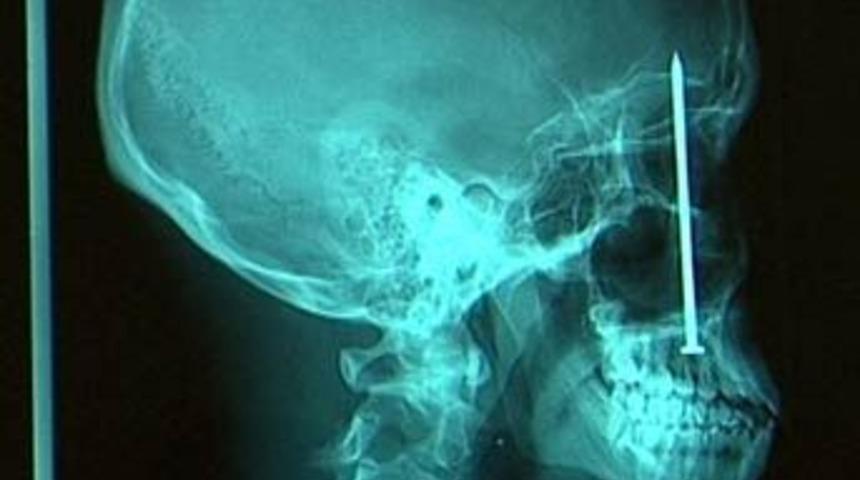

10 yaşındaki Husky cinsi bu köpek oynarken yuttuğu çatal yüzünden büyük bir tehlike atlattı. Midesi delinen köpek ameliyat edilerek kurtarıldı. Londrada başına bıçak saplanan 16 yaşındaki bu çocuk bir mucize eseri kurtuldu. Bu röntgen filmi ise İngilterede bir bisküvi fabrikasında çalışan Anne Kellowa ait. Kellowun Annesinin evlilik yüzüğünü yutan ufak kız çocuğunun röntgen filmi.